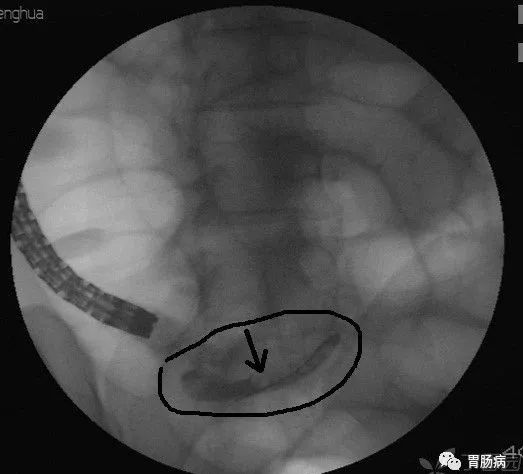

X线下,阑尾腔内注入造影剂显示阑尾腔的形态(椭圆形线圈),如有粪石(黑箭头),则行球囊取石术。并确认有无阑尾穿孔。

图B示阑尾腔内黏膜光整(椭圆形线圈),无炎症表现。